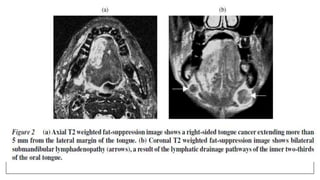

• Ong CK, ChongVFH. Imaging of tongue carcinoma.Cancer Imaging. 2006; 6: 186–193

• Law CP, Chandra RV, Hoang JK, Phal PM. Imaging the oral cavity: key concepts for the radiologist.The

British Journal of Radiology; 84 (2011): 944–957